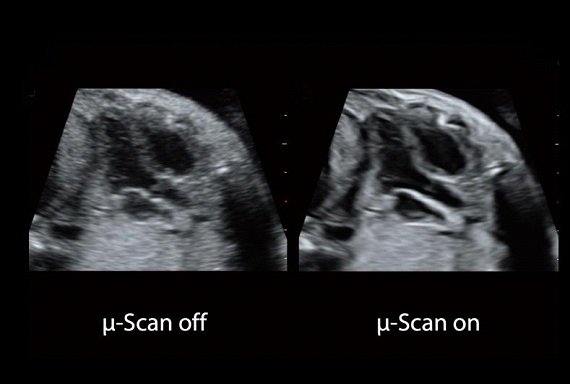

A Latest generation μ-Scan+, Play major role in B- Mode and 3D/4D modes, is more delicately engineered to distinguish tissue and artifacts, Improves the visibility of organs and Lesions in B Mode & Enhanced the B-Mode Resolution . In the meantime control the Speckle noise , improving image uniformity and enhance border continuity.